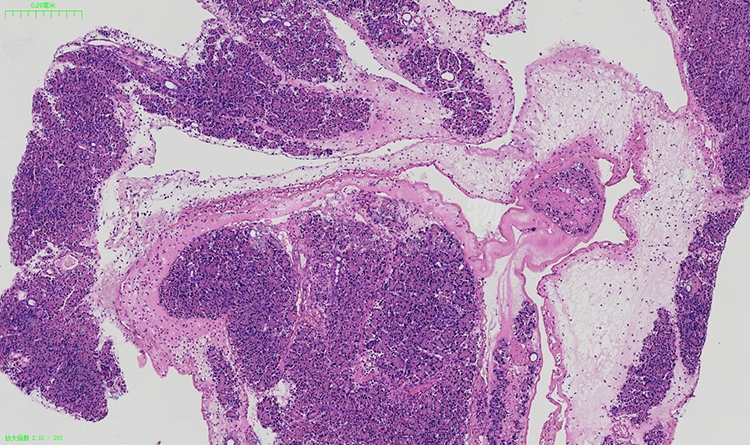

石蜡切片及染色是组织学研究中常用的技术,用于制备组织切片并进行显微镜观察。下面列举一些关于石蜡切片及染色的注意事项。

石蜡切片及染色